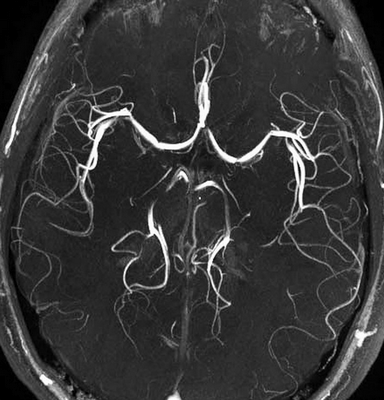

Стрелками на МР-томограммах отмечены участки демиелинизации нервных волокон. Слева - фото спинного мозга (сагиттальная проекция шейного отдела позвоночника), справа - головного (аксиальная плоскость)

Как выглядит рассеянный склероз на МРТ?

Диагностика рассеянного склероза позволяет выявить полную картину патологических изменений. Типичной считается следующая локализация очагов поражения:

Рассеянный склероз на МРТ головного мозга выглядит как пятна округлой формы диаметром до 2 сантиметров, которые по мере развития патологии могут сливаться. Оттенок измененных участков зависит от стадии болезни и бывает светлым, темным или идентичным здоровым тканям (без контраста не выделяется).

“Пальцы Доусона” на МР-томограммах в аксиальной (слева) и сагиттальной (справа) проекциях - выглядят на Т1 ВИ как светлые продолговатые очаги

Классическим признаком рассеянного склероза на МР-снимках головного мозга являются бляшки линейной формы, располагающиеся перпендикулярно боковым желудочкам. Их называют “пальцы Доусона”.